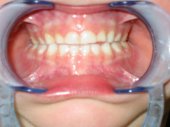

Una mordida cruzada anterior es el inicio visual

de una progenie mandibular. Sólo si se frena y corrige a una edad

temprana, que es cuando se originan, recupera de manera efectiva el desarrollo

normal.